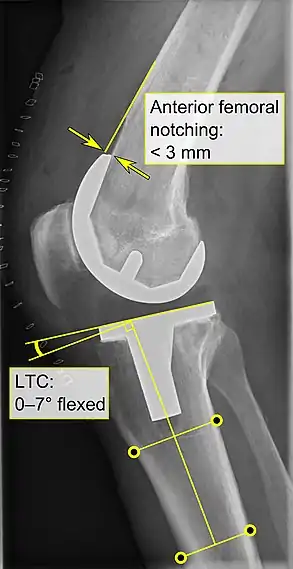

El reemplazo de rodilla se evalúa de forma rutinaria mediante rayos X, incluidas las siguientes medidas:

- CFF: ángulo del componente femoral frontal. Por lo general, se considera óptimo cuando se encuentra entre 2 y 7° en valgo.[55]

- CTF: ángulo del componente tibial frontal, que se considera óptimo cuando se encuentra en ángulo recto. En general, se ha encontrado que una posición en varo de más de 3 ° aumenta la tasa de falla de la prótesis.[55]

- La entalladura femoral anterior (el componente femoral que causa una reducción del grosor del fémur distal en la parte anterior) parece aumentar el riesgo de fracturas cuando excede aproximadamente 3 mm.[56]

- CTL: ángulo del componente tibial lateral (o sagital), que está idealmente posicionado de modo que la tibia esté flexionada de 0 a 7° en comparación con un ángulo recto con la placa tibial.[55]